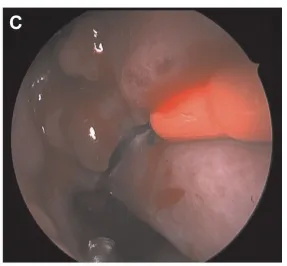

▼由下向上、由后向前切开右侧下鼻腔粘膜斜向切开(图C和D)。